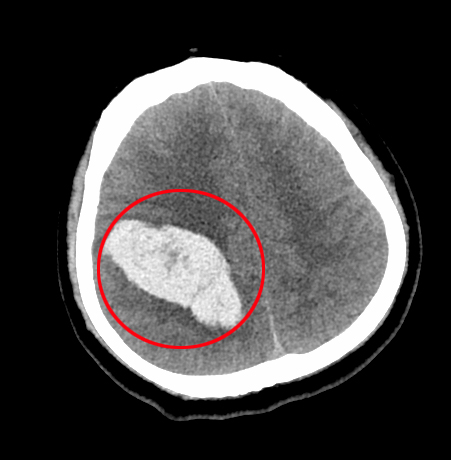

患者是家中独子,一直成绩优异,承载着父母的全部期望。他在课堂上毫无征兆地晕倒,校医紧急拨打120急救电话,把患者送往潞河医院。急诊神经外科值班医生王森接到通知后,迅速冲向抢救室,通过询问病史和查体,初步判断为脑出血,情况十分危急,随即上报给神经外科主任张洪兵。经过急诊CT检查,显示患者脑部血管畸形破裂出血,病变位于功能区,压迫语言中枢与运动皮层。若不及时救治,将严重影响其语言和行动能力,甚至危及生命。张洪兵主任果断指示开通绿色通道,全力抢救。

得益于潞河医院复合手术室的先进配置,血管造影检查和外科手术无缝衔接。经脑血管造影确诊为脑血管畸形。医生们面对患者出血部位在大脑重要功能区的复杂情况深知手术难度巨大,但家属给予的充分信任让大家坚定了信念。王长江和胡艳龙副主任医师通过三维重建技术精准定位血管畸形的供血动脉,在麻醉科和手术室医护人员的紧密配合下,复合手术开始了。血管造影精准定位责任血管,介入医生应用栓塞技术栓塞部分高危出血动脉,张洪兵主任在手术显微镜下仔细清除血肿、切除畸形血管团,每一步都需要高度专注和精湛技艺。术中还采用实时电生理监测技术,确保语言和运动功能不受影响。经过七个多个小时的奋战,手术顺利结束。

脑出血

脑血管畸形